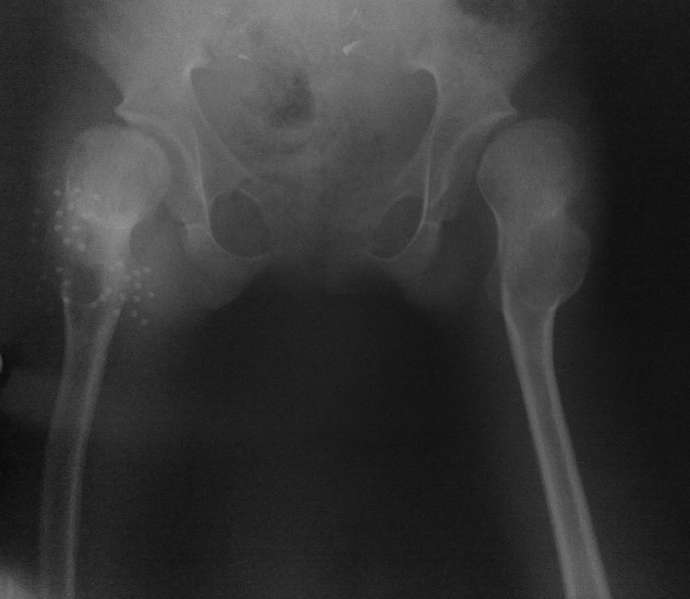

Ребенку 14 лет. 3 недели назад дома упала. На рентгенограмме диагностирован вывих в правом тазобедренном суставе.

Под общим наркозом вправлен. 2 недели ребенок находился на лейкопластырном вытяжении. В связи с тяжким состоянием ребенка (диспептические явления, задержка стула, носовые кровотечения, начальные явления застойной пневмонии) вытяжение снято. сразу после чего сделано рентген контроль (фото 1). а через неделю, то есть сегодня сделан второй снимок (фото 2). Где видно повторный вывих.

На рентгенограмме видно, что в 3 месячном возрасте не была диагностирована тяжелая форма дисплазии с подвывихами, где, кроме вывиха, имеет место непролеченные диспластические суставы с обеих сторон, больше справа.